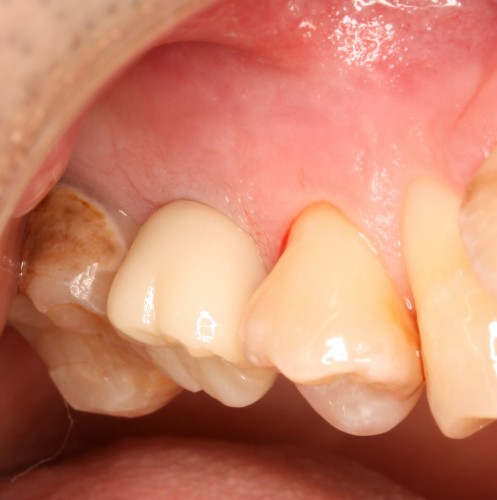

被せ物装着

被せ物装着後歯肉の盛り上がり